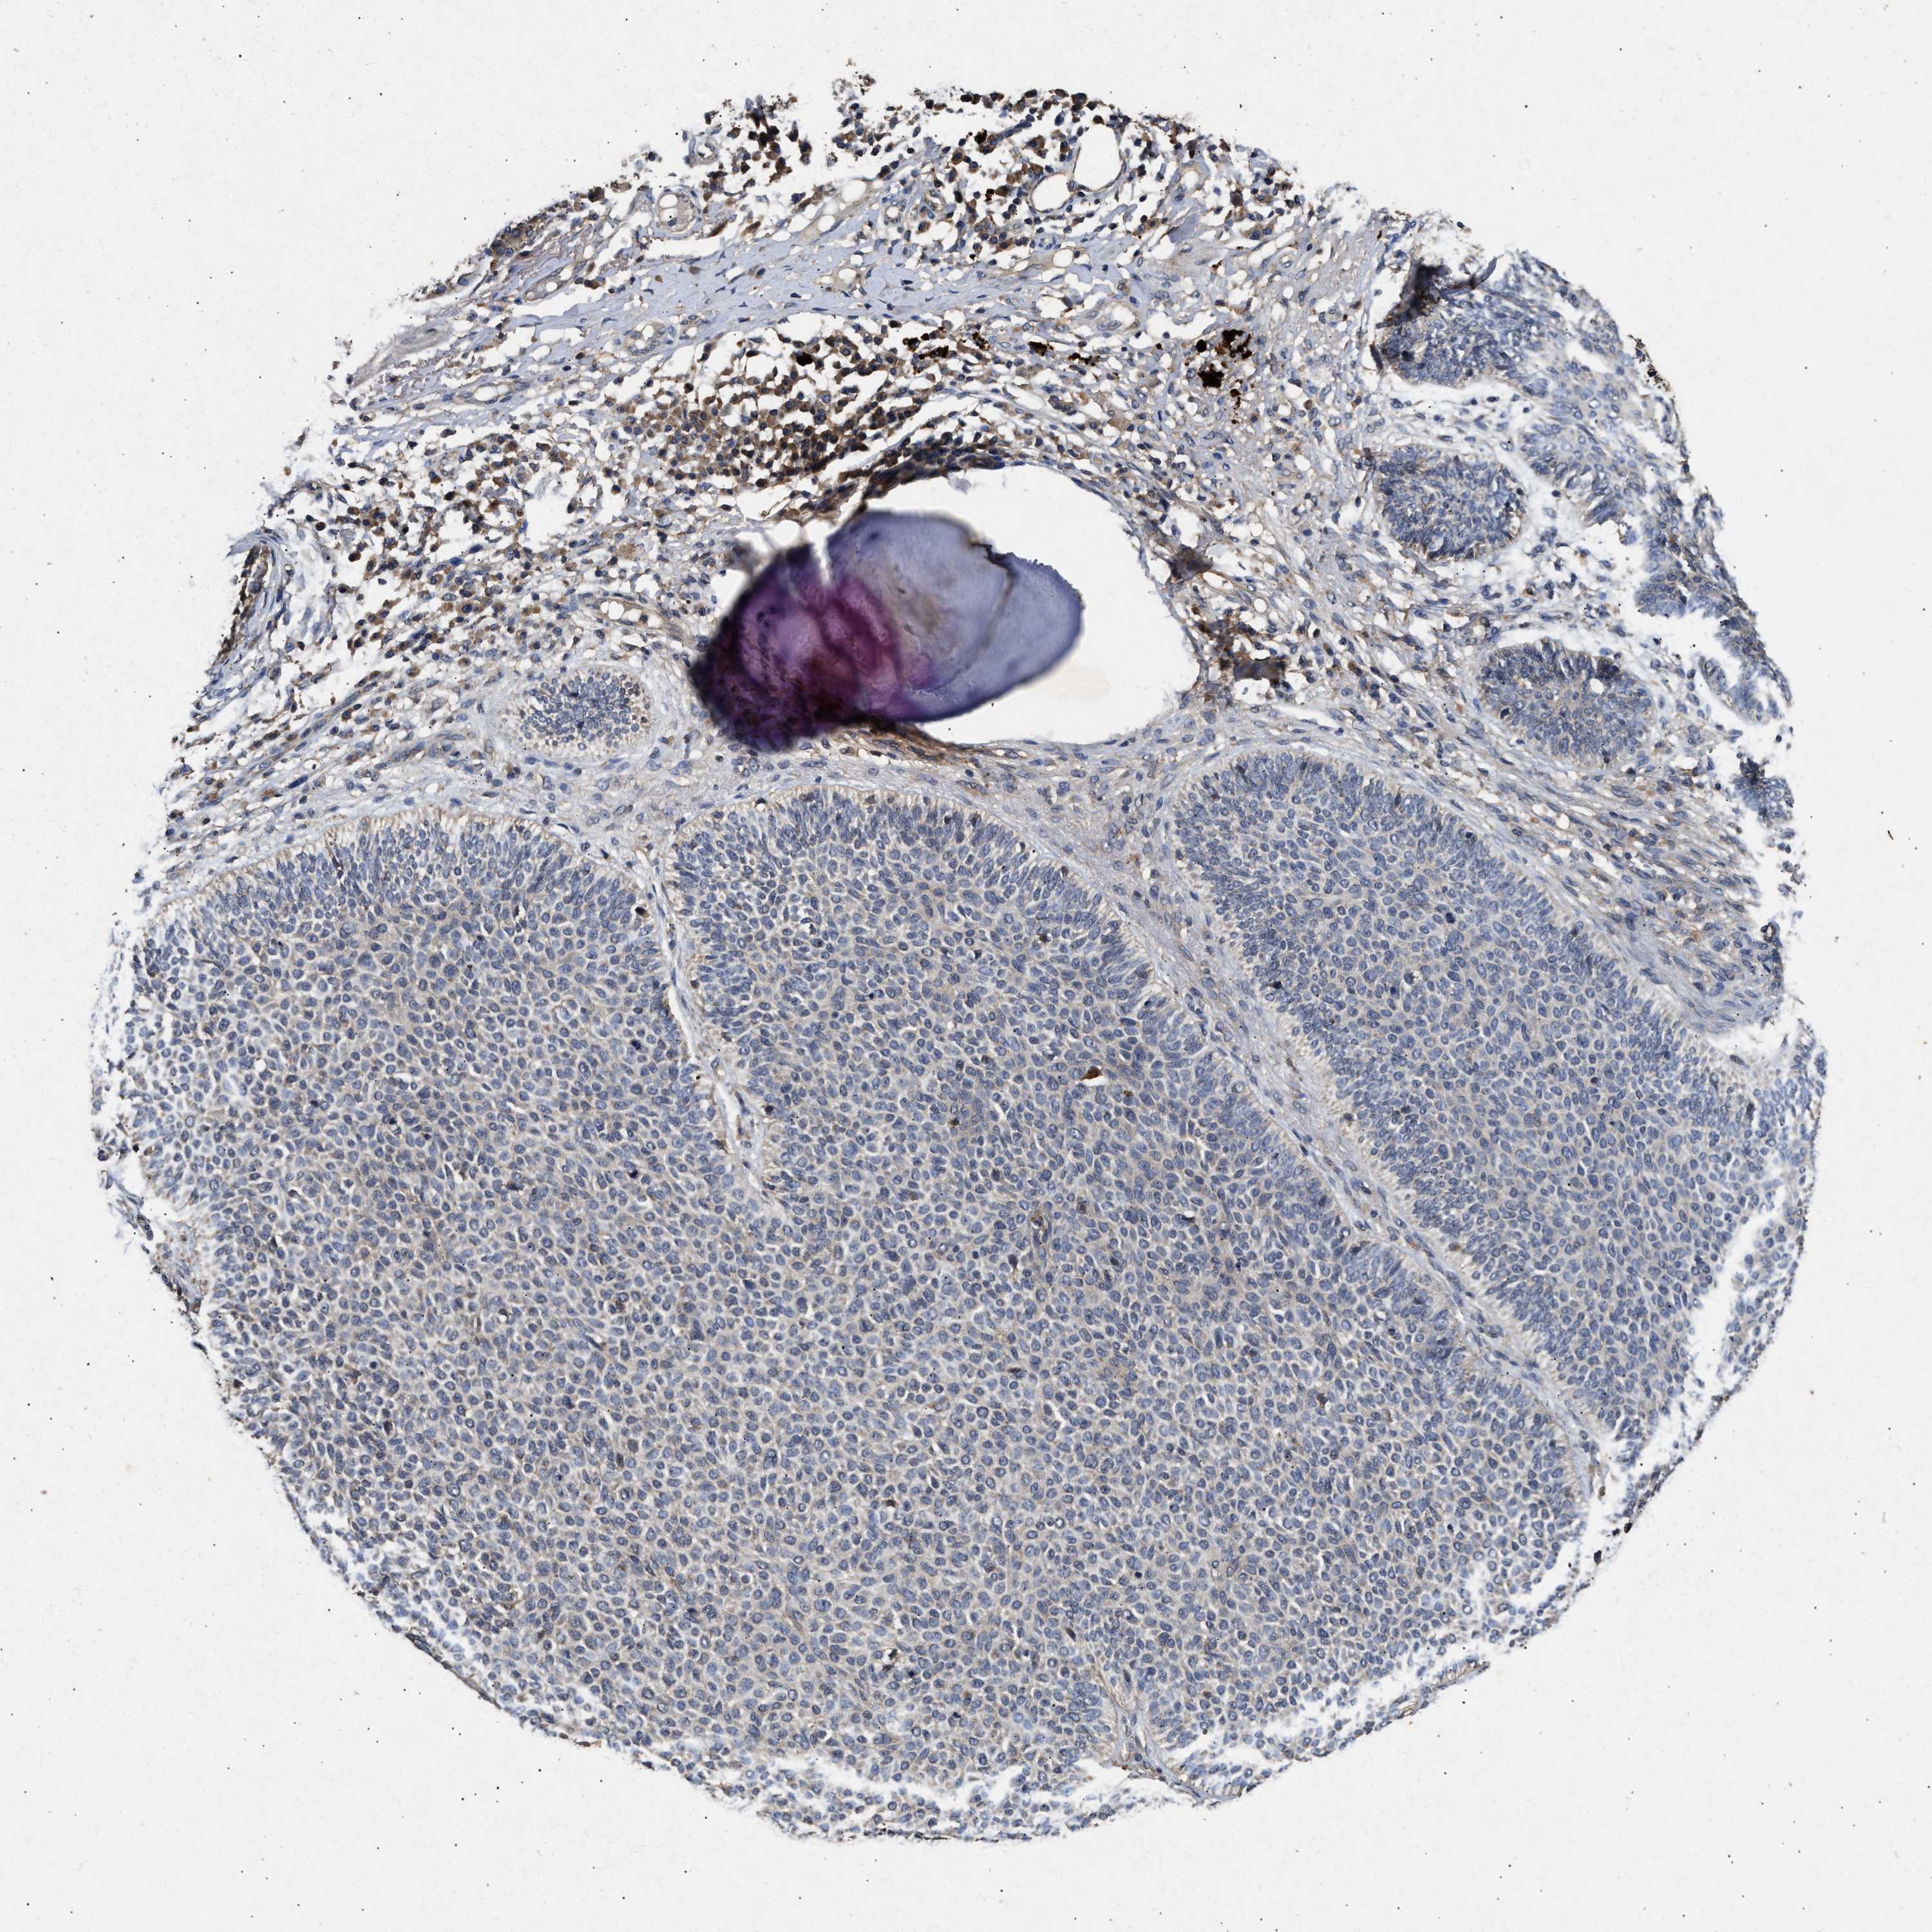

SKIN CANCER - Protein expressioni

A mouse-over function shows sample information and annotation data. Click on an image to view it in a full screen mode. Samples can be filtered based on level of antibody staining by selecting one or several of the following categories: high, medium, low and not detected. The assay and annotation is described here.

Each image is clickable and will lead to virtual microscopy that enables deeper exploration of all samples and also displays staining intensity scores, fraction scores and subcellular localization as well as patient and tissue information for each sample.

Antibody HPA050294

Antibody HPA060836

Antibody CAB021103

Staining

High

Medium

Low

Not detected

Intensity

Strong

Moderate

Weak

Negative

Quantity

>75%

75%-25%

<25%

None

Location

Nuclear

Cytoplasmic/membranous

Cytoplasmic/membranous,nuclear

Basal cell carcinoma

Squamous cell carcinoma, NOS